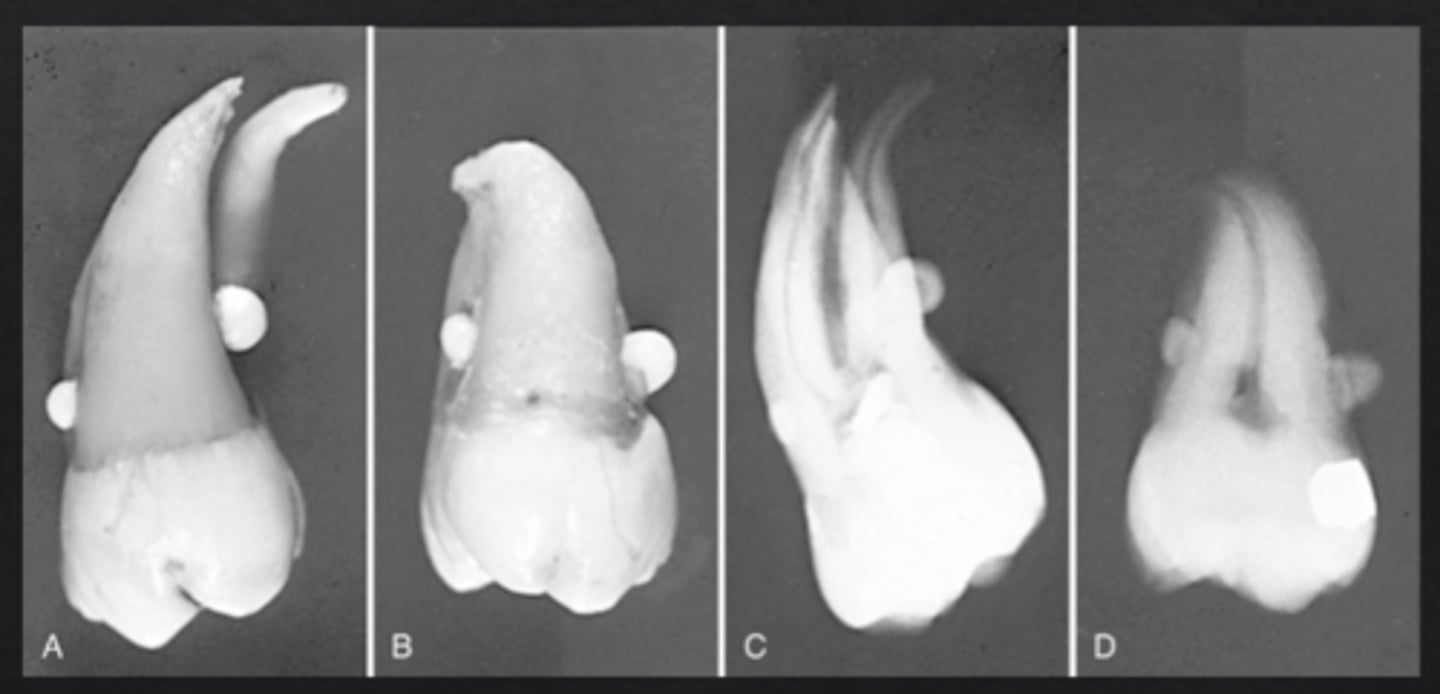

What is an odontoma?

Benign odontogenic tumor composed of enamel, dentin, cementum, and pulp

What is a compound odontoma?

Forms multiple small tooth-like structures with recognizable layers of dental antomy

What is a complex odontoma?

Disorganized mass of dental tissues without a tooth-like form